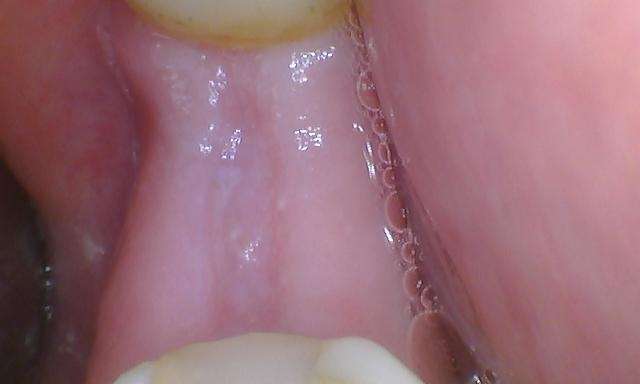

A patient visited our clinic in Mount Waverley with a missing second molar. After a thorough evaluation, we determined that a dental implant would be the best solution. We proceeded with the implant procedure, and we placed an implant crown. The result is a fully restored molar, providing the patient with improved function and aesthetics.